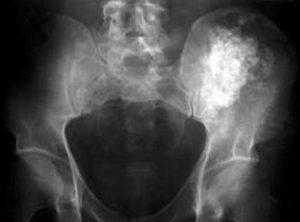

Большинство опухолей позвоночного столба обнаруживается при обычных обследованиях, проводимых при наличии болей в шее или пояснице. Обследование начинается с физического осмотра. При наличии опухолей в других органах необходимо информировать врача так, как это необходимо для адекватного обследования. Рентгенография применятся для диагностики костных изменений в позвоночнике. Но результаты рентгенографии не достаточно информативны. И когда возникает необходимость более четкой визуализации, как костной ткани, так и мягких тканей, то назначается КТ или МРТ. Кроме того, при подозрении на злокачественную опухоль в позвоночнике может быть назначена сцинтиграфия. Лабораторные исследования необходимы для уточнения характера опухоли и возможных осложнений со стороны других органов и систем (особенно при злокачественных опухолях).

Анкилозирующий спондилит (болезнь Бехтерева). Это заболевание является разновидностью артрита, при котором происходит хроническое воспаление суставов позвоночника, крестцово-подвздошных суставов. Первоначально, воспаление возникает в крестцово-подвздошных суставах, затем переходит в позвоночник, приводя к скованности и ограничению подвижности. При длительном воспалении суставов позвоночника (спондилите), образуются депозиты кальция в связках вокруг межпозвоночных дисков, что приводит к ослаблению дисков и снижению их амортизационной и опорной функций. По мере накопления депозитов кальция в связках происходит значительно снижение, как объема движений, так и гибкости в позвоночнике. Болезнь может прогрессировать до сращения позвонков, что называется анкилозом. В результате анкилоза позвоночник теряет мобильность, позвонки становятся хрупкими, увеличивается риск перелома позвонков. Кроме повреждения позвоночника болезнь Бехтерева приводит к нарушениям в работе других органов, так как заболевание это системное.

Остеопороз заболевание, при котором происходит ослабление костной ткани, в том числе и позвонков, что увеличивает риск перелома позвонков, даже при незначительных нагрузках. Компрессионные переломы позвоночника являются наиболее распространенным типом переломов, обусловленных остеопорозом, также возможны при остеопорозе переломы бедра и запястья. Эти переломы позвонков могут изменить форму и прочность позвоночника, особенно у пожилых женщин, у которых на фоне таких переломов нередко возникает деформация позвоночника. Позвоночник приобретает избыточный наклон в грудном отделе (кифоз) и выпиранию плеч вперед. При выраженном остеопорозе даже простые движения, такие как наклон вперед, могут привести к перелому позвонков.

Компрессионные переломы

Как следует из названия, компрессионные переломы возникают от чрезмерных осевых нагрузок, что нарушает целостность тела позвонка. Остеопороз является одной из ведущих причин компрессионных переломов, так как происходит снижение способности позвонков выдерживать нагрузки. В таких случаях даже легкое падение или даже кашель могут привести к компрессионному перелому. Люди часто воспринимают боль в спине, как нормальный процесс старения, и подчас компрессионные переломы остаются незамеченными. Повторные компрессионные переломы могут приводить к уменьшению высоты позвоночника. Другой распространенной причиной компрессионного перелома является травма, такая как падение.